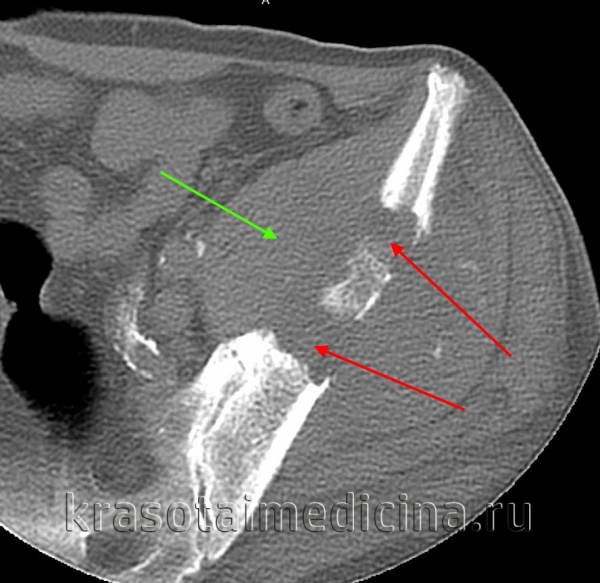

КТ таза. Метастатическая карцинома подвздошной кости слева с деструкцией костной ткани (красная стрелка) и обширным мягкоктанным компонентом (зеленая стрелка)